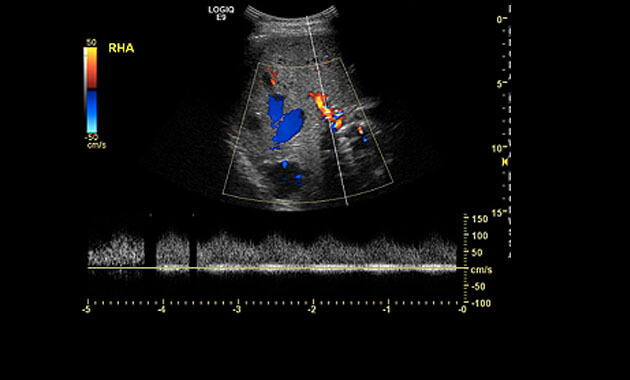

Ultrasound depicting a

Liver Arteriovenous Malformation (AVM).

Screening

A liver ultrasound uses reflected sound waves to produce a picture of the organs in the abdomen. No radiation is used during this study, and it is therefore the preferred method for screening liver AVMs.